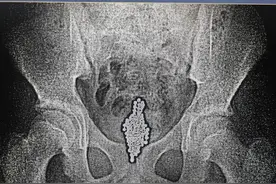

开学都1个月了,但16岁的男孩小林(化名)却再次住进医院进行后续治疗。暑假结束前,他怎么也没想到因为自己贪玩游戏,竟患上年轻人中少见的“下肢深静脉血栓”,险些危及生命。庆幸的是,经过医护人员的努力,成功为他清除了身体里长达七八十厘米的血栓。